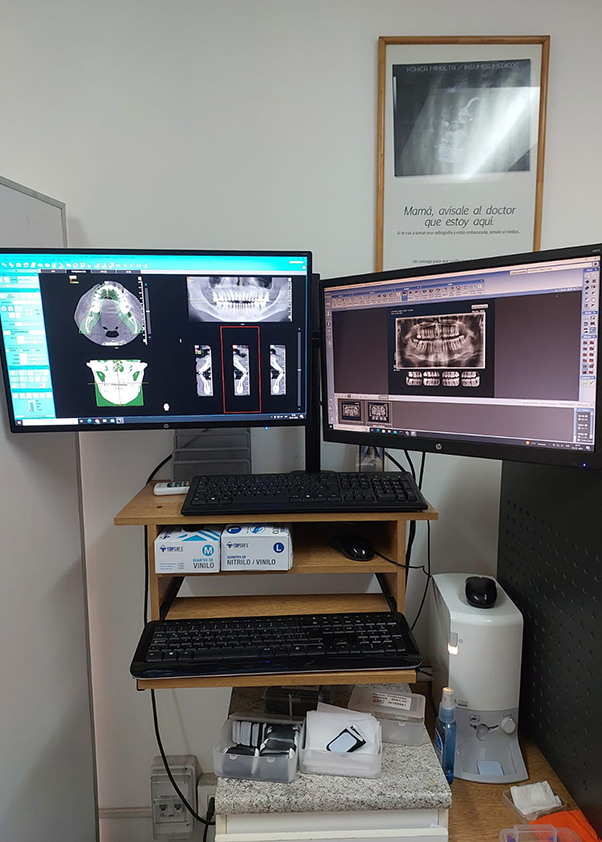

Todas nuestras prestaciones están orientadas a proveer la mejor imagen e informes diagnósticos del territorio Oral y Máxilo Facial, entre las que se cuentas técnicas retroalveolares, radiografías panorámicas, telerradiografías y estudios radiográficos de articulaciones témporo mandibulares (ATM)

Radimax es un centro de Radiología Oral y Máxilo Facial que cuenta con el más moderno sistema de adquisición y procesamiento de imágenes, como también con personal que posee los más altos estándares de conocimiento del área, lo que en su conjunto forman, tanto para el profesional como para el paciente, la mejor opción a la hora de elegir un apoyo diagnóstico radiológico

Al preferir Radimax, tendrá la seguridad que sus pacientes recibirán la mejor atención del área, especialista con formación universitaria y un respaldo académico-clínico del más alto nivel, lo que finalmente se traducirá en exámenes e informes que contribuirán efectivamente al diagnóstico